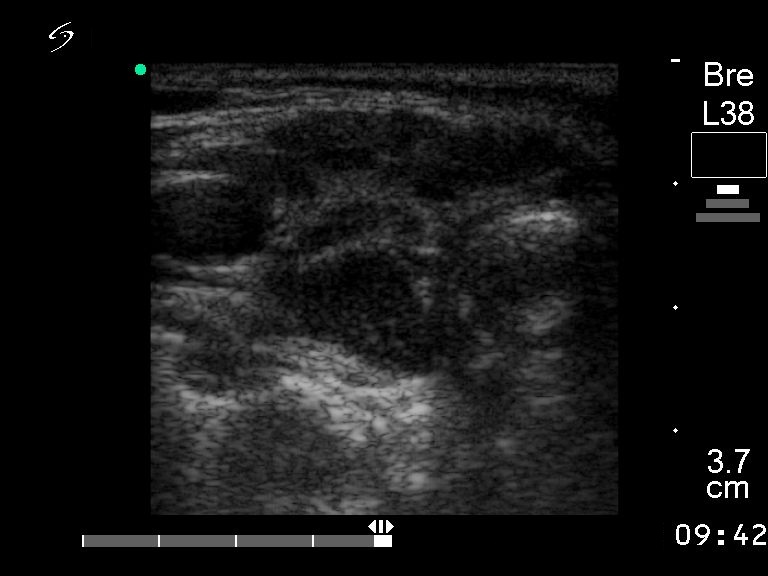

First examination (first and second rows of images):

Clinical presentation: a 55-year-old woman with hypothyroidism replaced with 50 ug levo-tiroxin.

Functional state: euthyroidism.

Ultrasonography: the echogenicity index is around 50% in both lobes. The circumscribed lesions are not nodules. Previous US diagnosis was multinodular goiter.

Combined ultrasound-cytological report : benign Hashimoto's thyroiditis.